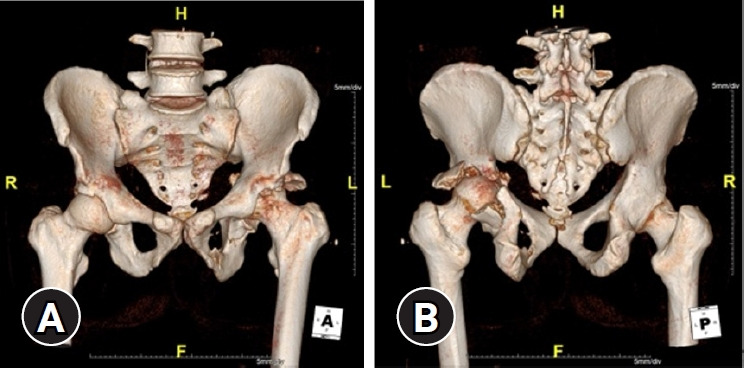

骨盆骨折是由高能创伤引起的,当伴有失血性休克时,死亡率增加到40%。骨盆骨折在解剖学上分为骨盆环断裂和髋臼骨折,每种骨折需要不同的治疗方法和入路。髋臼骨折也可由高能损伤引起,并可伴有失血性休克。盆腔骨折合并失血性休克的治疗选择包括血管栓塞、腹膜前盆腔填充物(PPP)和紧急剖腹手术。对于血流动力学稳定的患者,可以尝试早期全面护理,对于髋臼骨折(后柱),Kocher-Langenbeck入路是治疗的选择。本病例报告描述了在Kocher-Langenbeck入路治疗髋臼骨折伴骨盆环损伤的术后腹膜后出血伴血流动力学不稳定的抢救手术中使用PPP。患者出院时无骨移位或手术部位感染等术后并发症。虽然PPP通常被用作盆腔骨折并失血性休克的初始治疗方式,但它在治疗术后腹膜后出血并失血性休克方面也可能有价值。

Pelvic fractures result from high-energy trauma, and when accompanied by hemorrhagic shock, the mortality rate increases to 40%. Pelvic fractures are anatomically categorized as pelvic ring disruptions and acetabular fractures, each requiring different treatment methods and approaches. Acetabular fractures, which also result from high-energy injuries, may be accompanied by hemorrhagic shock. Treatment options for pelvic fractures with hemorrhagic shock include angioembolization, preperitoneal pelvic packing (PPP), and emergency laparotomy. In hemodynamically stable patients, early total care may be attempted, and for acetabular fractures (posterior column), the Kocher-Langenbeck approach is the treatment of choice. This case report describes the use of PPP as a salvage operation for postoperative retroperitoneal bleeding with hemodynamic instability following a Kocher-Langenbeck approach for an acetabular fracture with pelvic ring injury. The patient was discharged without postoperative complications such as bone displacement or surgical site infection. While PPP is commonly employed as an initial treatment modality for pelvic fractures with hemorrhagic shock, it may also be valuable in managing postoperative retroperitoneal bleeding with hemorrhagic shock.